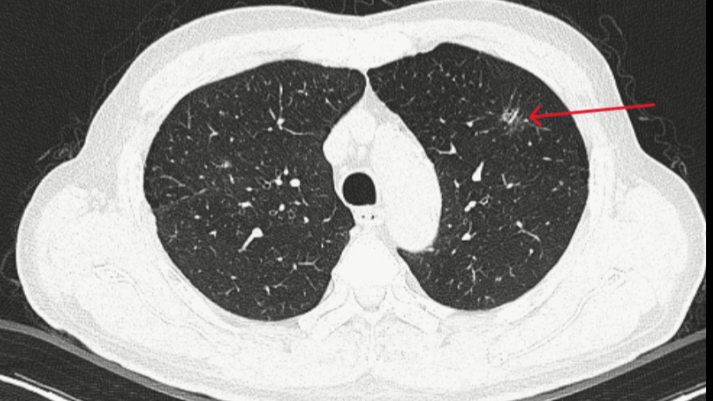

Tại Bệnh viện Bạch Mai, nam bệnh nhân ở Ninh Bình được AI phát hiện tổn thương thùy phổi phải và nguy cơ ung thư ác tính. Bệnh nhân đến khám tổng thể, không có dấu hiệu gì điển hình, ngay khi chụp X quang cũng chỉ phát hiện có đám mờ ở phổi.

Dù được làm thêm các xét nghiệm cận lâm sàng khác như nội soi phế quản, cuống họng... cũng chưa có gì đáng chú ý. Tuy nhiên, khi đưa các chỉ số của bệnh nhân vào phần mềm và AI hỗ trợ phân tích cho thấy, bệnh nhân được xác định bị tổn thương ở thùy phổi phải và nguy cơ ung thư ác tính.

Từ gợi ý đó, bác sĩ quyết định cho bệnh nhân chụp CT lồng ngực. Kết quả đúng như phân tích, máy tự động đọc và nhận diện ra tổn thương với đám mờ phổi chính là triệu chứng thời kỳ đầu của ung thư phổi.